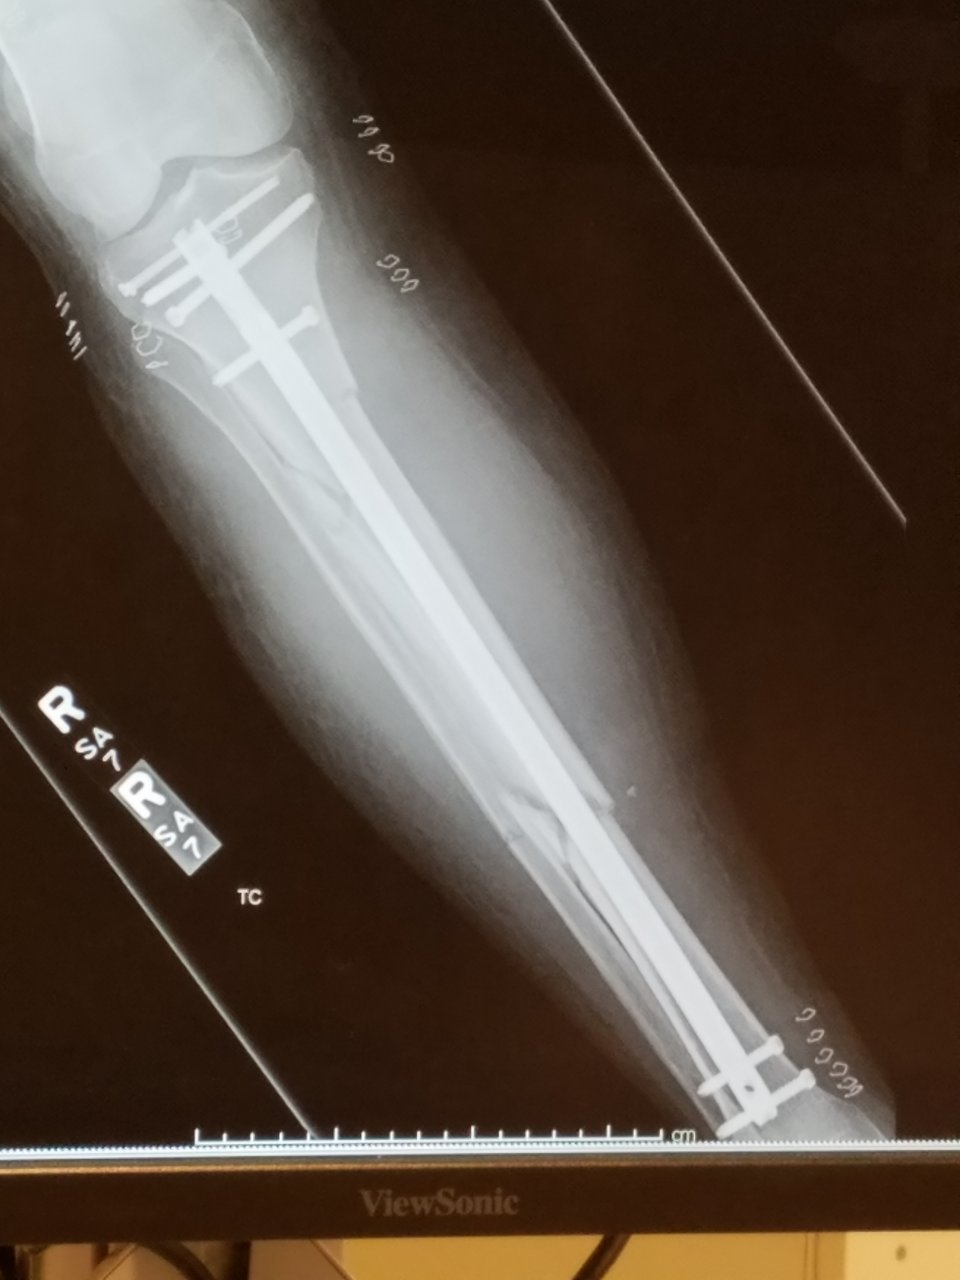

TSA is gonna have a ball with me from now on...

20210915_113559.jpg

Does this mean you're officially a cyborg?